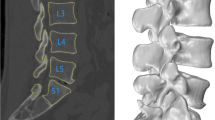

Ten asymptomatic subjects (M/F: 5/5; age: 40–60 years) were recruited. The lumbar segment of each subject was MRI-scanned to construct 3D models of the L2–S1 vertebrae. The lumbar spine was then imaged using a dual fluoroscopic imaging system as the subject performed a weight-lifting activity from a lumbar flexion position (45°) to maximal extension position. The 3D vertebral models and the fluoroscopic images were used to reproduce the in vivo vertebral positions along the motion path. The relative translations and rotations of each motion segment were analyzed.

Experiment setup

A validation study was performed to evaluate the accuracy of the DFIS technique when used to determine human lumbar spine kinematics during dynamic motion. In this validation, a cadaveric human body segment from feet to chest was acquired. The body segment included the entire lumbar spine and had all the surrounding soft tissues intact. Titanium beads (MRI compatible) of 4 mm in diameter were implanted into the L3, L4 and L5 vertebrae by a spine surgeon (Fig. 5). The lumbar spine was then MRI-scanned using the protocol described in the Sect. “Materials and methods”. The contours of L3, L4, L5 vertebrae and the beads were digitized from the MR images to reconstruct their 3D mesh models. A local coordinate system was created for each spine vertebral segment model as described in our previous study [35]. The specimen was then placed in a sitting position and the lumbar spine was manually flexed to simulate a dynamic physiologic flexion–extension motion at a rotation speed of ~50°/second. The test was guided using a timer. Dynamic orthogonal images of the lumbar spine were taken simultaneously from the anteromedial and anterolateral directions using two fluoroscopes (Fig. 2a).

The spatial positions of the vertebral bodies during the flexion–extension motion were reproduced in Rhinoceros® software through 3D to 2D imaging matching (Fig. 6), as described in the Sect. “Materials and Method”. To evaluate the accuracy of the image matching technique of DFIS in reproducing vertebral motion, five positions were chosen along the dynamic motion path of the spine: maximum flexion, middle flexion, upright, middle extension and maximum extension. Each position was independently reproduced using both the vertebral body matching technique (DFIS method) and the beads position matching technique (RSA method––gold standard) [35]. The positions and orientations of each vertebra determined using the DFIS and RSA methods were compared to evaluate the accuracy of the DFIS method in determination of dynamic lumbar kinematics.